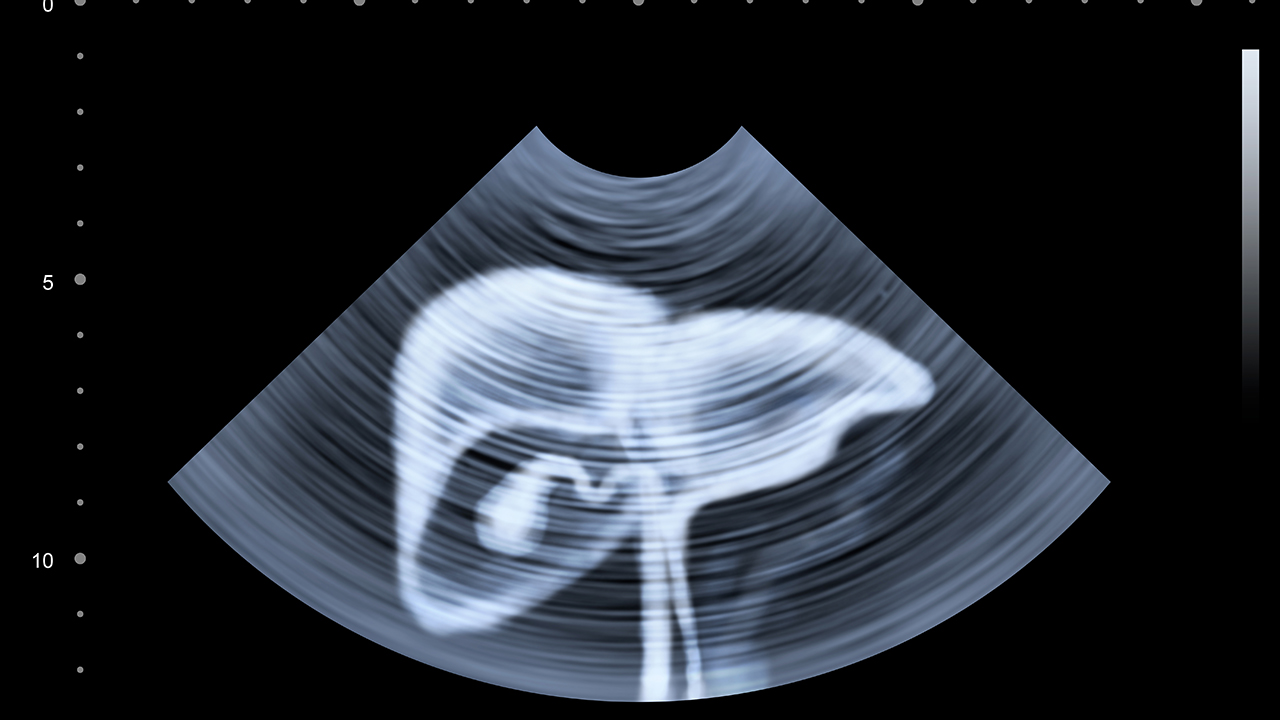

肝癌的預(yù)防與健康管理至關(guān)重要。首先,接種乙肝疫苗可以有效預(yù)防乙肝病毒感染,從而降低肝癌的發(fā)生風(fēng)險(xiǎn)。其次,避免長期酗酒和食用霉變食物,減少黃曲霉素的暴露。對(duì)于慢性肝病患者,應(yīng)定期進(jìn)行肝功能檢查和肝臟超聲篩查,早期發(fā)現(xiàn)病變。此外,保持健康的生活方式,如均衡飲食、適量運(yùn)動(dòng)和規(guī)律作息,有助于維護(hù)肝臟健康。對(duì)于已經(jīng)確診的肝癌患者,應(yīng)積極配合醫(yī)生治療,定期復(fù)查,保持良好的心態(tài),提高治果和生活質(zhì)量。